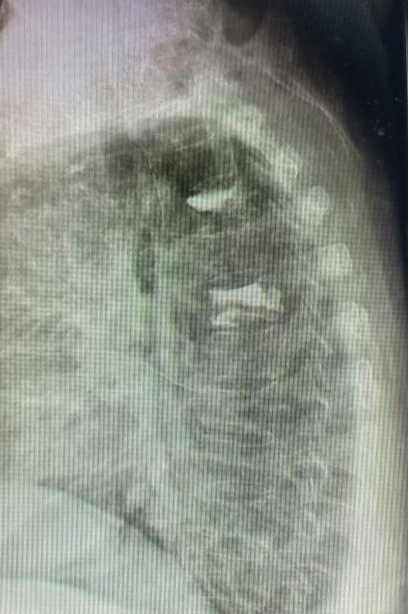

粤西网讯(陈华明 黄跃)日前,廉江市人民医院脊柱外科成功完成首例第3胸椎体压缩骨折经皮穿刺椎体成形术,此次手术为廉江市人民医院首例。手术后X线片复查显示椎体内骨水泥填充良好,无骨水泥渗漏。手术后患者疼痛症状明显缓解,患者满意。

经手术前讨论及充分的手术前准备,近日,由主任医师况光荣主刀,副主任医师陈华明、副主任医师邓训训为助手,介入科团队全力配合实施手术,手术获得圆满成功。患者第二天即可下地行走,疼痛症状完全消失后出院。